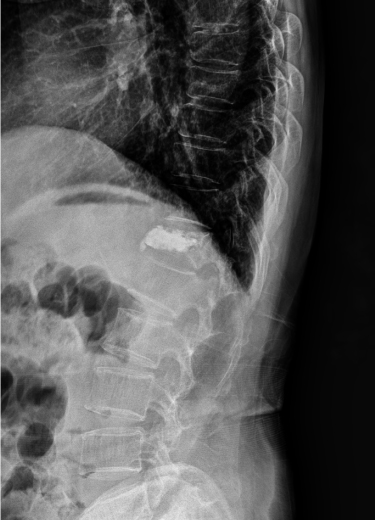

척추 골절

교통사고나 낙상 등에 의한 충격에 척추 골절이 발생하기도 하며, 대부분 고연령층에서 골다공증성 골절로 발생하는 경우가 많습니다.

척추압박골절은 골절 유합은 물론 장기적인 합병증이 발생하지 않도록 주의해야 합니다.

또, 대부분 고령 환자이거나 내과적 기저질환을 앓고 있는 환자로 심각함 골다공증 상태에서 척추 손상이 재발하면 추가적인 골절 위험성이 매우 크므로 골절 치료뿐 아니라 주기적인 골다공증 검사 및 예방으로 환자의 전신상태를 관리해 주는 게 중요합니다.

척추 골절에서 발생하는 문제점

□ 2차적인 변형을 초래할 수 있어 이로 인해 신경압박이나 만성 신경병증 후유증이 남을 수 있음

2021.12.21

2021.12.27